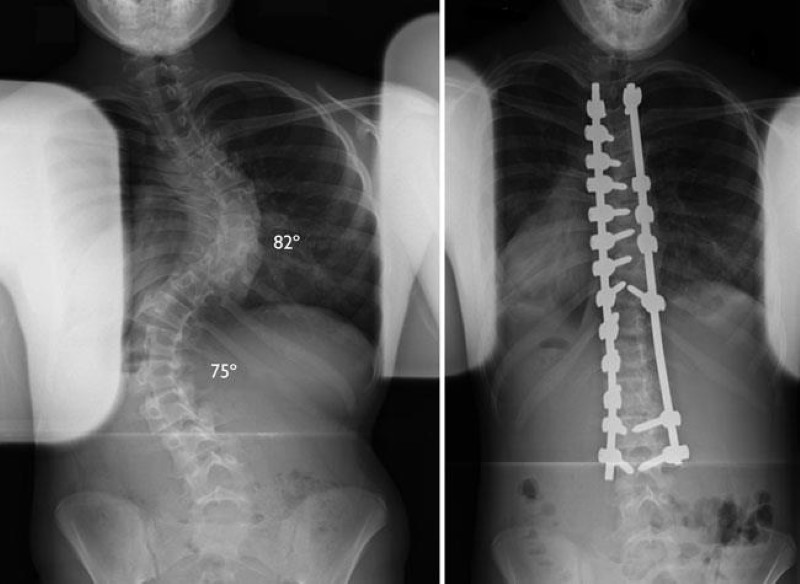

Scoliosis surgery is designed to address significant structural changes in the spine. In simple terms, it aims to stabilise the spine, improve overall alignment, and reduce further progression of the curve when specific clinical criteria are met.

The most common form of scoliosis surgery involves realigning sections of the spine and securing them with specialised implants such as rods and screws. These implants hold the spine in a corrected position while the bones gradually heal and stabilise over time. Surgery focuses on spinal balance and stability in the long run.